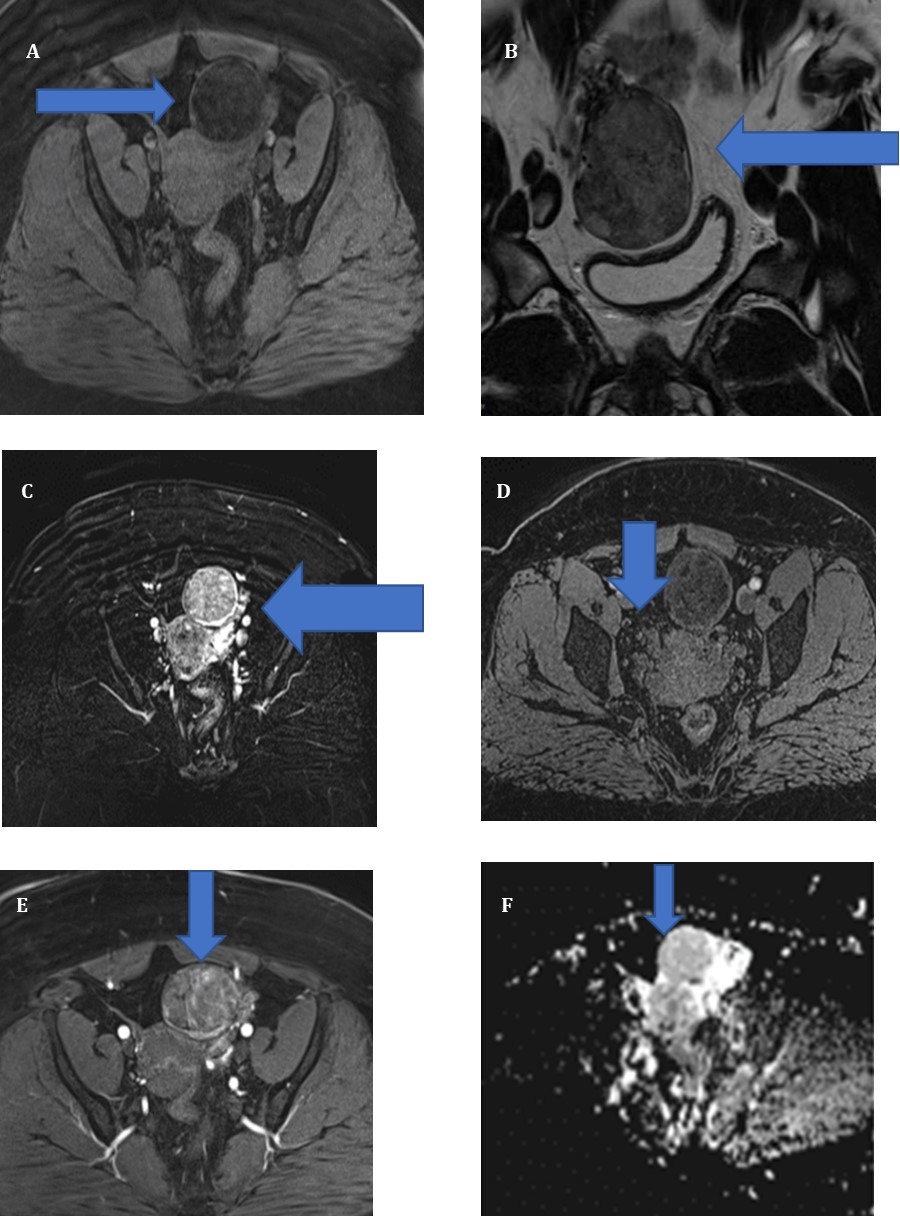

Une IRM realized without and with contrast Gadolinium, in sequence T1,T2, DIFFUSION and confirmed one left masse ovarian

(Figure 1) , ( A, B) Axial T1-Weighted image shows (6 cm) ovoid hypointense masse (arrows) in left adnexal region. Ill- defined area of high signal intensity is noted, indicating lipid content. On T2-weighted image, masse (arrows) is heterogeneously hyperintense(C). After gadolinium administration, T1-weighted image shows tumor (arrows) is very intensely enhanced (D,E,F). F, diffusion image

Figure 1A.Sequence T1 without contrast B) Sequence T2 without contrast c) T2 with contrast GADO D) Sequence T1 with contrast GADO E) Sequence T1 with contrast GADO F) Sequence diffusion